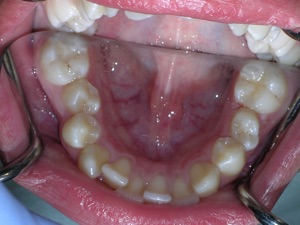

In this case, a young woman came to us with a desire to straighten her teeth. We elected to do Invisalign treatment with some enamel reduction and some dental arch expansion. Take a look...

Here she is on the day of appliance removal. You can see how the crossbite on the right has improved, as well as the lower front teeth crowding. Note that we elected to leave the lower second premolar in it’s rotated form.